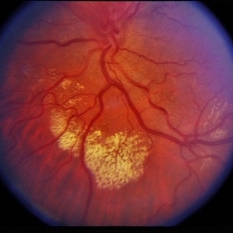

Retinal Capillary Hemangioblastoma

Feb 20 2015 by H. Michael Lambert, MD

Retinal capillary hemangioblastoma associated with Von Hippel-Lindau Disease. No history. Whitening around lesion possibly cryothermy or laser.

Condition/keywords: retinal capillary hemangioblastoma